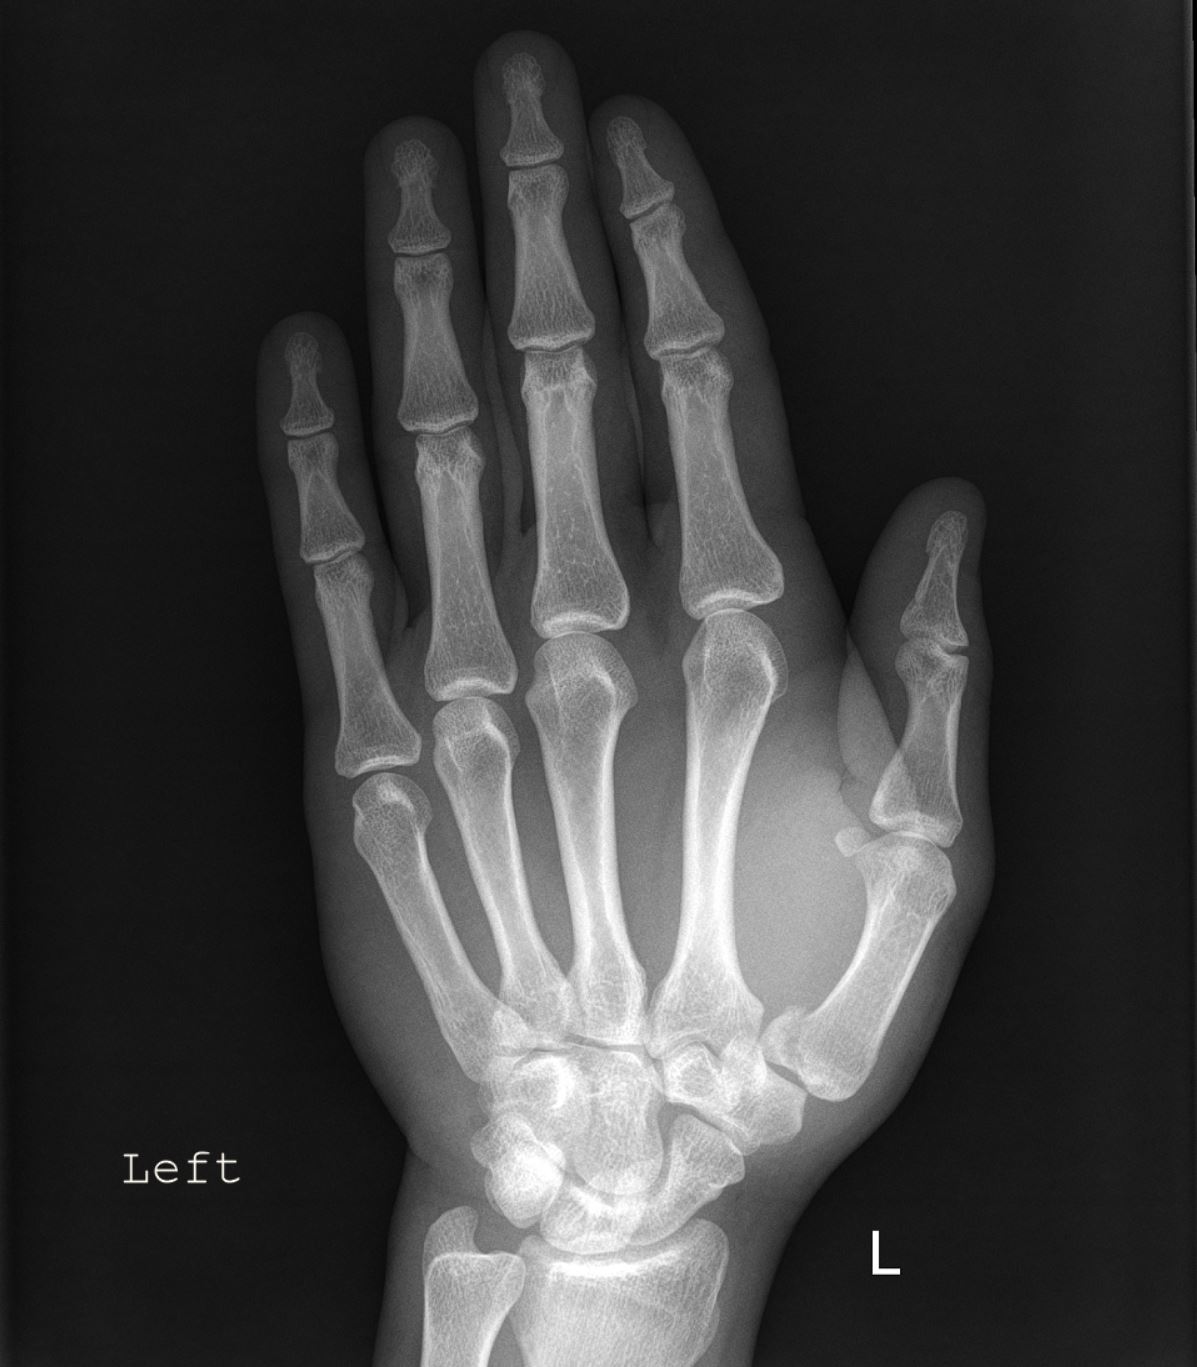

Sie haben folgende Anamnese in Ihrer Anforderung: Z.n. Sturz auf die linke Hand. Welche Verletzung erkennen Sie auf vorliegendem Röntgenbild?